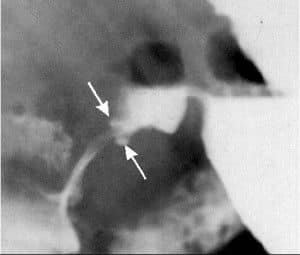

ULCUS

• ULCUS EN CURVATURA MENOR. NICHO ULCEROSO CON CONTRASTE Y PLIEGUES CONVERGENTES